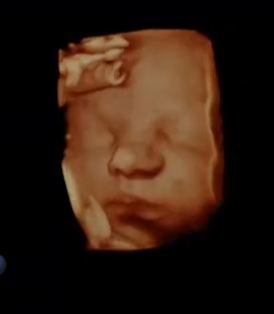

4D / HD ELECTIVE ULTRASOUNDS

Several Packages to Choose From

Text Jessie at least 2 Weeks Prior to Schedule Appointment

1-906-202-9378

Start drinking extra fluids 3 days prior to clear and add volume to Amniotic Fluid

Choose Package - Fill Out Liability Waiver - Text Jess to Schedule 906-202-9378